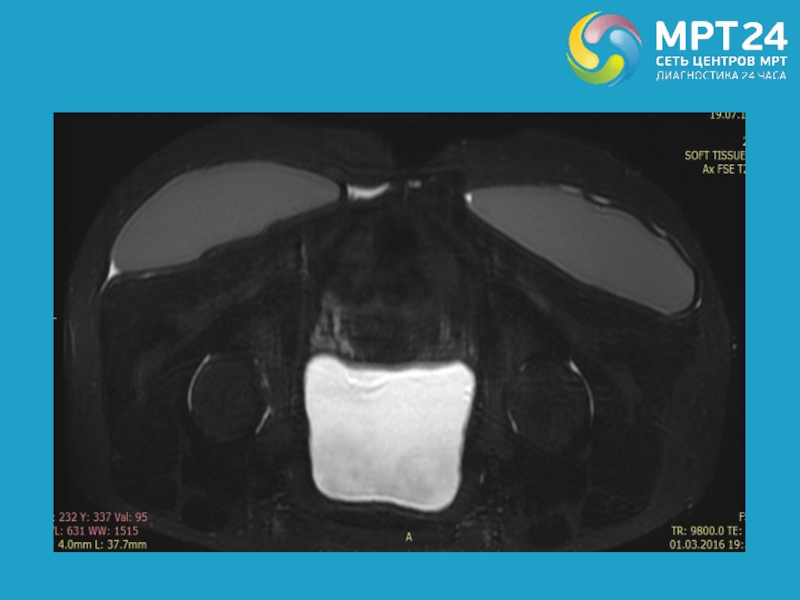

Слайд 24

Укладка пациента